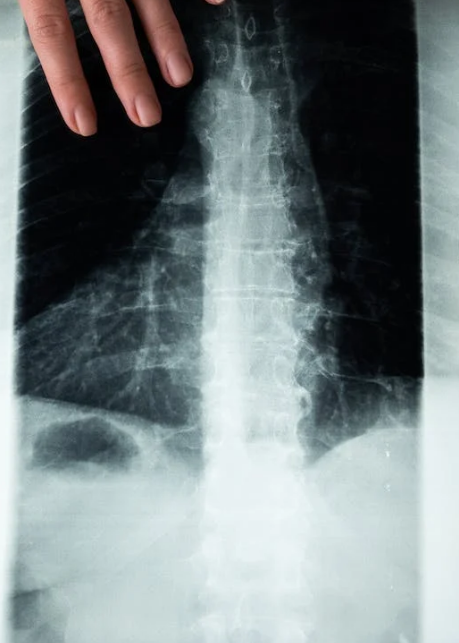

척추관협착증은 나이가 들면서 발생하는 척추의 퇴행성 질환 중 하나로, 허리 신경을 둘러싸고 있는 구조물이 변화함에 따라 허리 신경이 지나가는 공간이 좁아지는 상태를 말합니다. 이 변화는 척추뼈, 인대, 척추관절 등의 구조적인 변화로 인해 발생하며, 주로 허리 부위에서 발생하는 통증과 관련이 있습니다.

척추관협착증과 요추 추간판탈출증은 비슷한 증상을 보일 수 있지만, 그 발생 원인과 특징에서 차이가 있습니다. 요추 추간판탈출증은 디스크(추간판)의 이상으로 인해 발생하는 급격한 통증이 특징이며, 디스크의 찢어짐이나 흐름이 있을 때 주로 나타납니다. 반면 척추관협착증은 서서히 진행되는 퇴행적인 변화로, 통증이 수개월에서 수년에 걸쳐 서서히 나타날 수 있습니다.